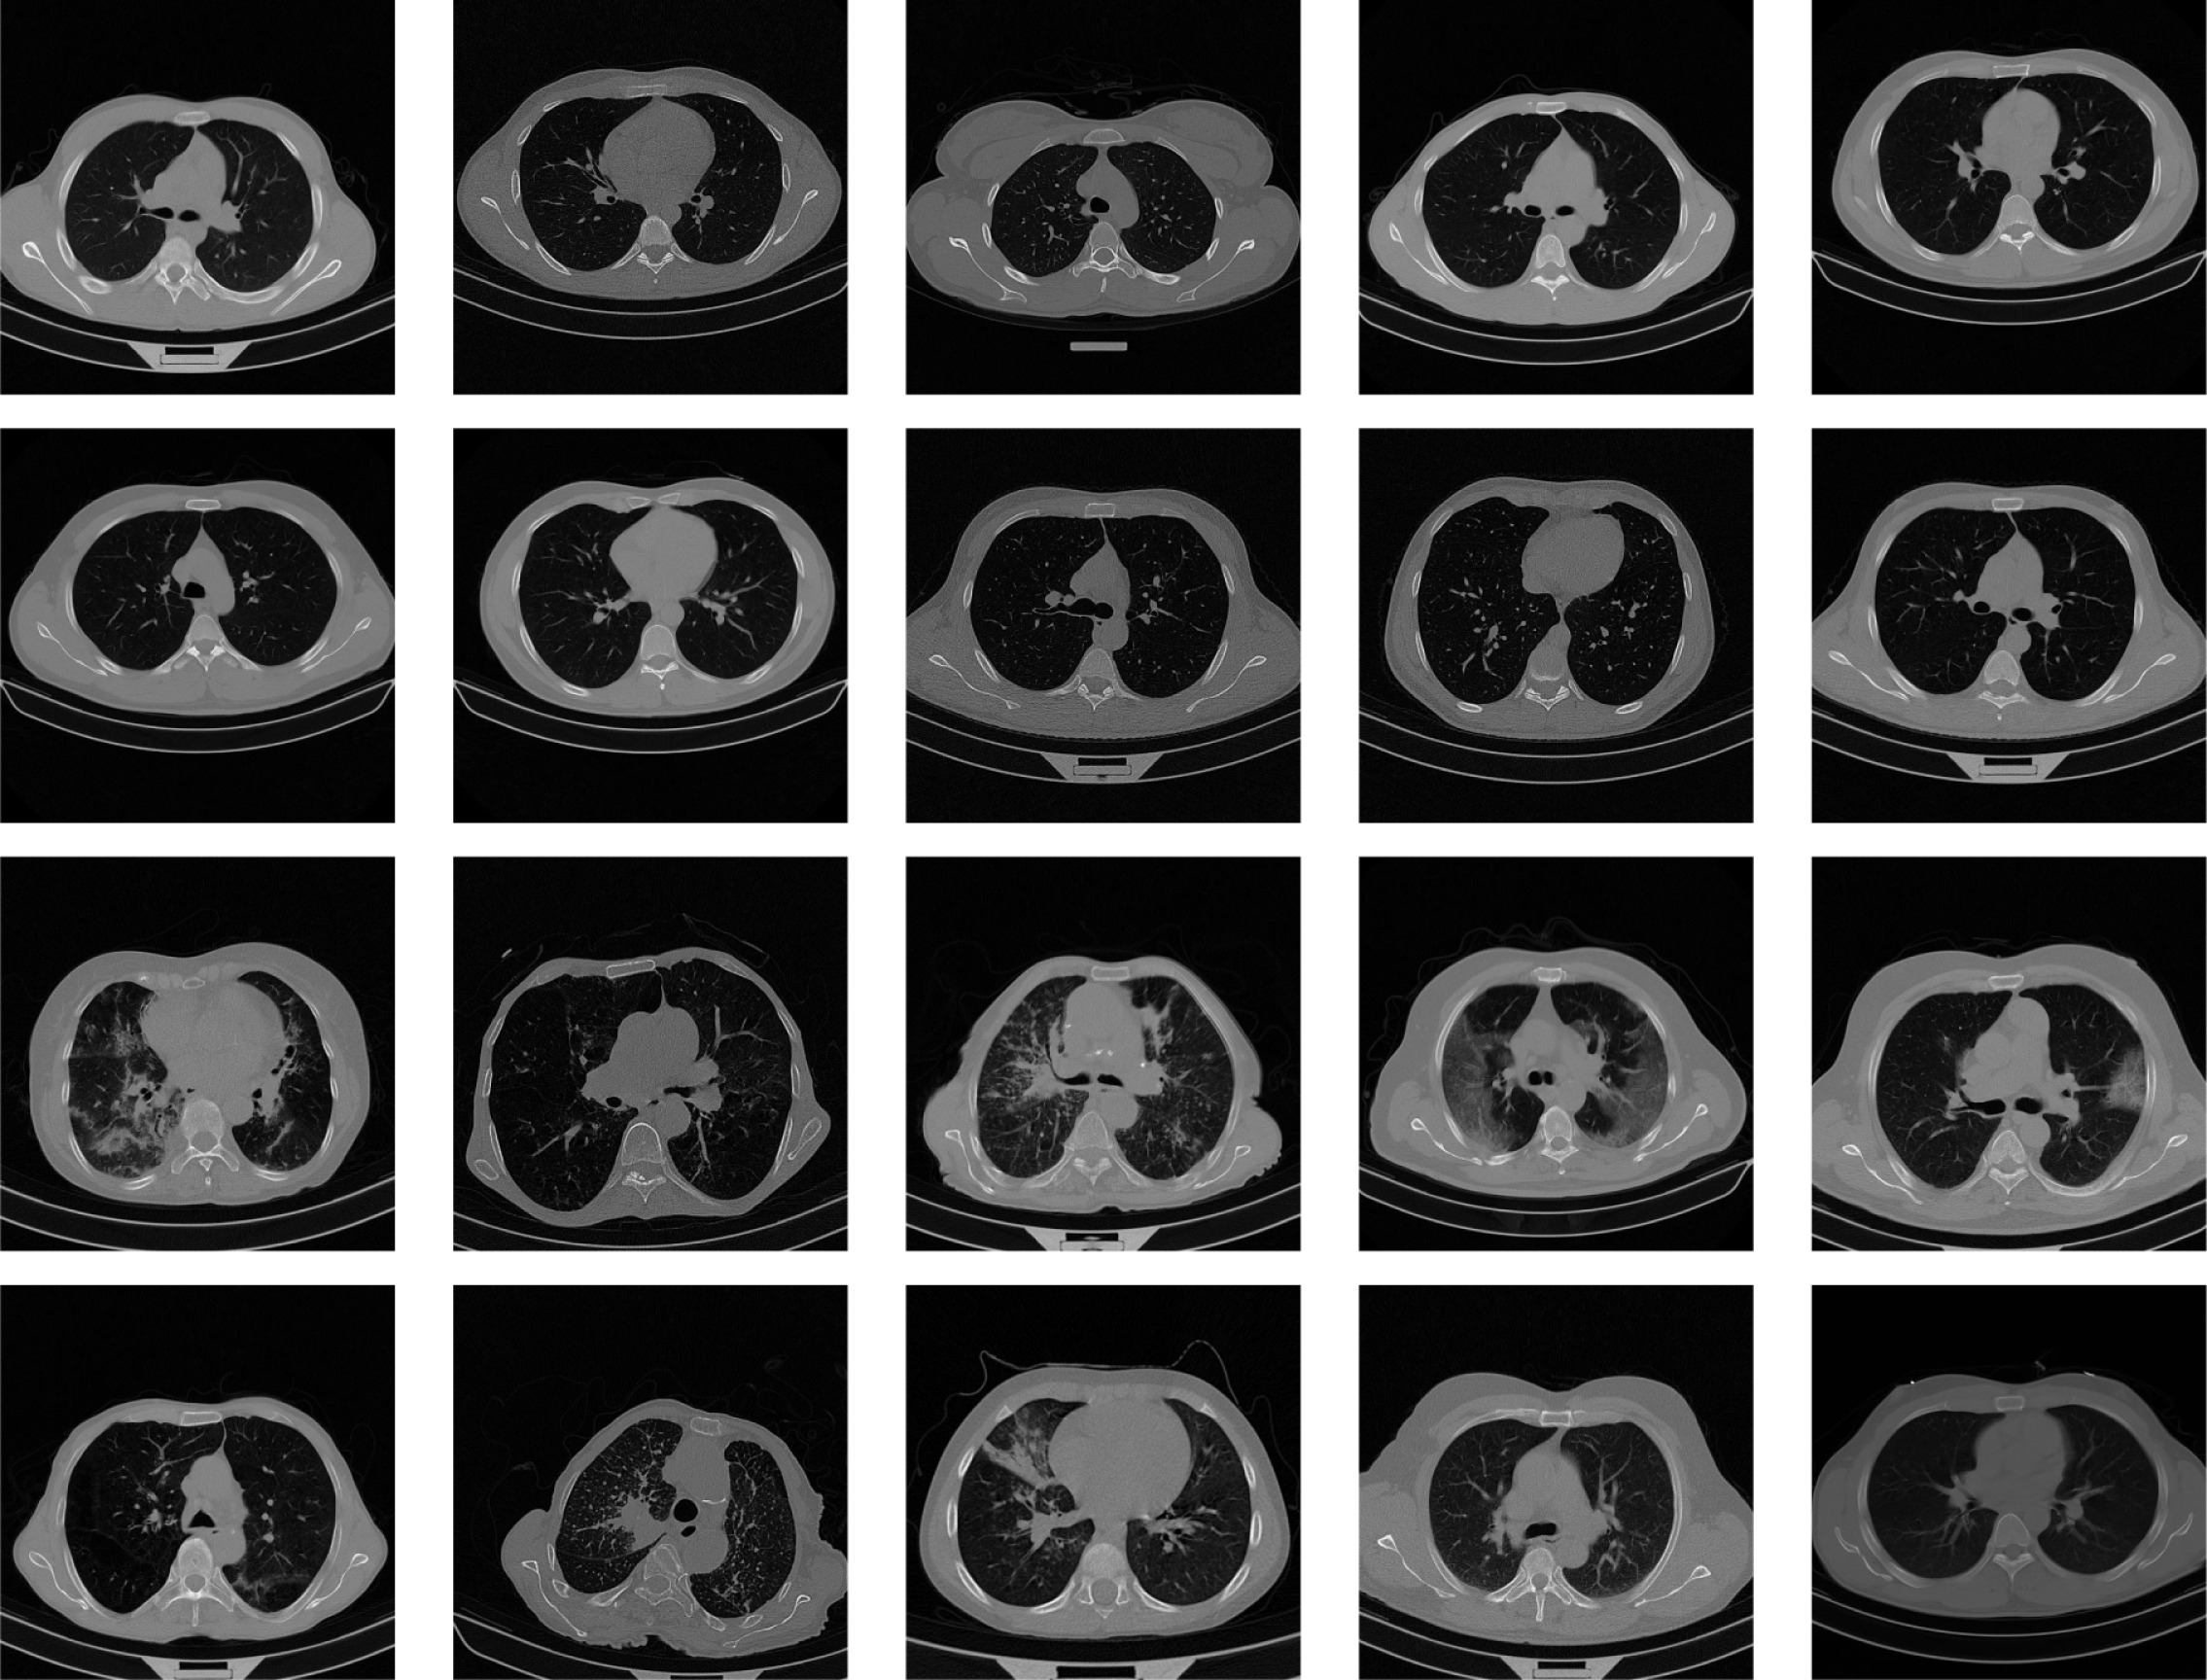

The second step is a meticulous region-of-interest (ROI) extraction and cropping process. This process is specifically designed to isolate the lung regions from the rest of the CT scan. It operates by first creating a binary mask of the lungs and then using contour finding algorithms to identify the two largest contours, representing the left and right lungs. Bounding boxes are then drawn around each lung. A key design choice is to crop each lung region separately and then resize both to a consistent size of 125x250 pixels before horizontally concatenating them into a single 250x250 pixel image. As shown in figure 3, this approach focuses the model exclusively on the diagnostically relevant pulmonary regions, removing extraneous information such as ribs, the heart, or background noise. By providing the model with a consistent, focused input, the feature learning process becomes more efficient and effective, which is a strong contributing factor to the final high performance.

Refer to caption

Figure 3: CT Scans and Cropped Lung Regions of COVID-19 CT segmentation dataset